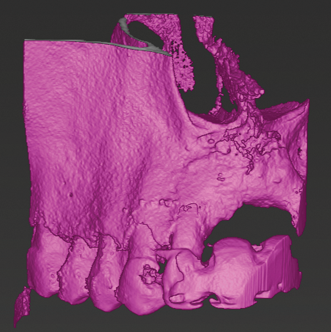

Advanced Treatment Planning Technologies

The use of IOSs in combination with other imaging modalities, such as CBCT and 3D facial scans, is playing a crucial role in advancing treatment planning in modern dentistry. This integration enables the creation of so-called "digital twins," ie, 3D models that precisely capture anatomical details and their spatial relationships. These digital twins enhance the precision of various dental interventions. When IOI data and data from facial scans are combined, they facilitate techniques such as digital smile design.7 Additionally, digital twins generated from the integration of IOI and CBCT support both static and dynamic navigation methods.8,9 This approach is increasingly being adopted across a range of clinical applications, including dental implant placement, orthodontic mini-implant placement, and endodontic access cavity preparation (Figure 6 through Figure 9).

Fig 6: CBCT imaging of a maxillary lateral incisor requiring root canal treatment.

Fig 7: Fusion of CBCT data (shown in magenta) with the IOI (shown in cyan).